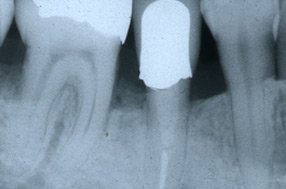

■歯周病治療例

歯周病の進行に伴う歯肉の

炎症と歯の移動が見られます。

歯周外科手術と同時に矯正で

歯周組織の再生と審美回復と

なりました。